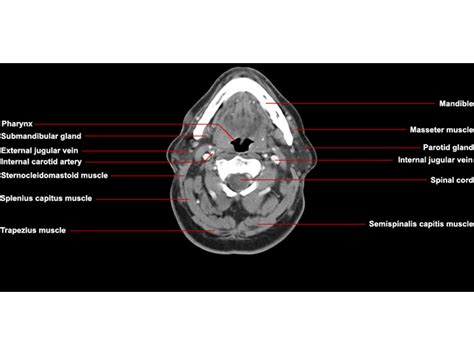

Back Muscles Anatomy Ct - CT scan of head and neck

CT Neck Axial Anatomy | RADIOLOGYPICS.COM

CT Neck Axial Anatomy | RADIOLOGYPICS.COM from radiologypics.files.wordpress.com

This image is titled back muscles ct anatomy and is attached to our article about best back muscles training exercises.